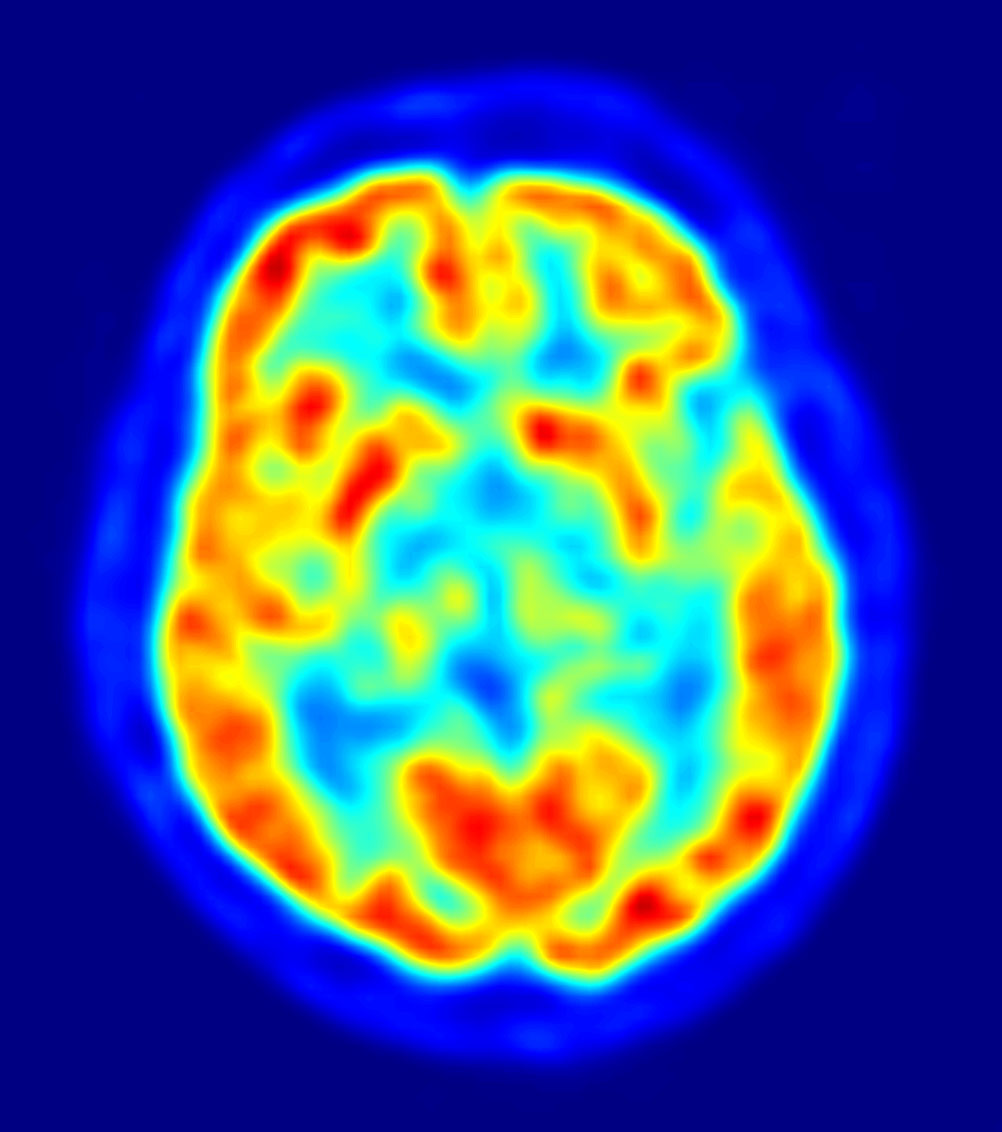

1. SPECT, PET: വിവിധ മസ്തിഷ്കഭാഗങ്ങളിലെ രക്തയോട്ടമളന്ന് അതിലേതൊക്കെയാണു കൂടുതല്‍ പ്രവര്‍ത്തനനിരതമെന്ന സൂചന തരുന്നു (ചിത്രം 1).

ചിത്രം 1

(ചിത്രങ്ങള്‍ക്കു കടപ്പാട്: ചിത്രം 1: neuroshrink.com ചിത്രം 2: neurocenter.unige.ch ചിത്രം 3: Human Connectome Project ചിത്രം 6: ibtimes.co.uk ചിത്രം 7: wikimedia.org ചിത്രം 8: tremorjournal.org ചിത്രം 9: kids.frontiersin.org ചിത്രം 11: Principles of Biochemistry)